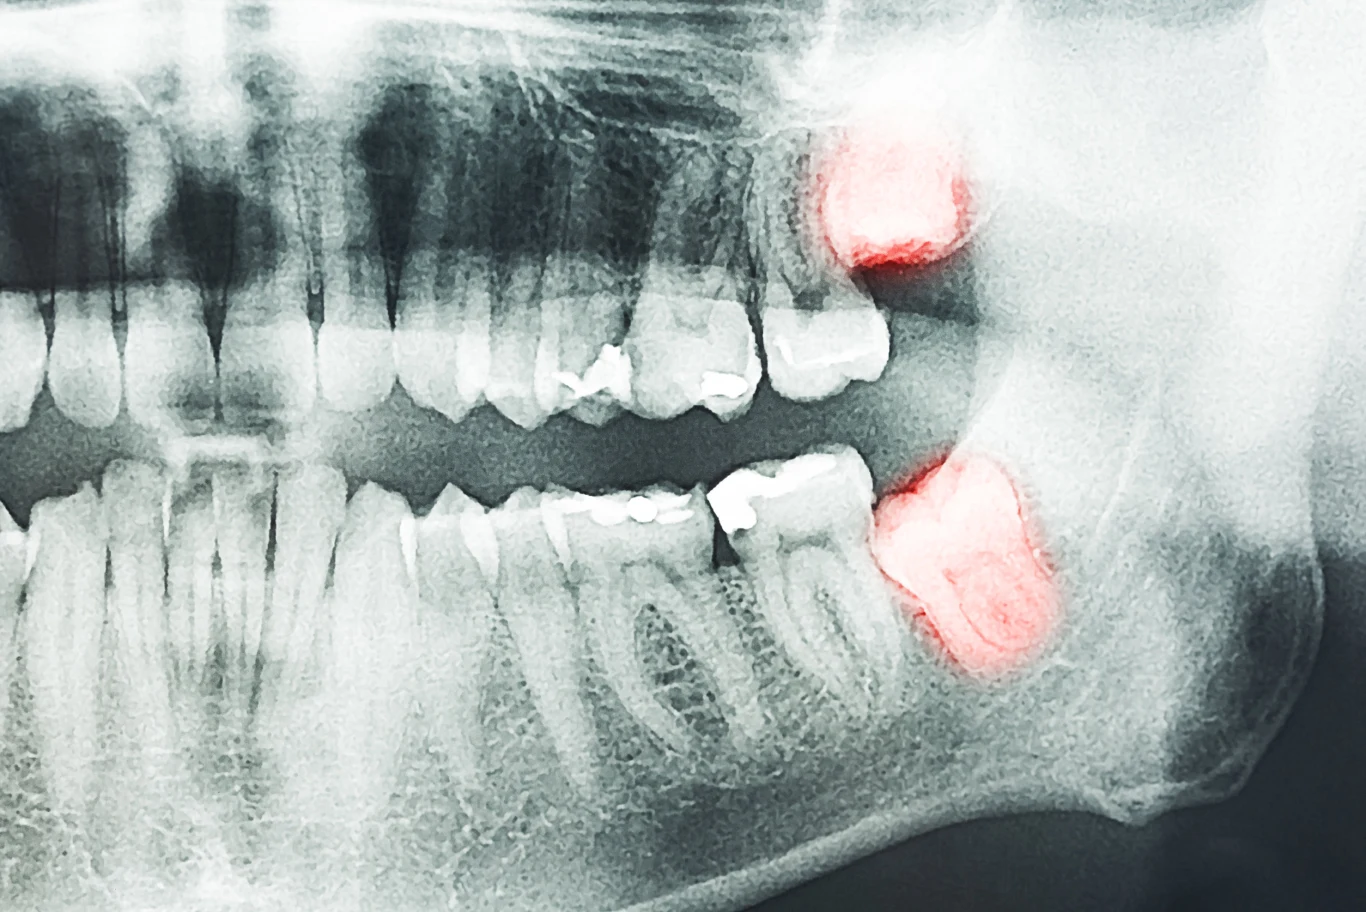

Zmiany w budowie ciała mogą dotyczyć szczęki i zębów. Już dziś ludzie mają mniejsze szczęki niż dawniej, przez co często brakuje miejsca na wszystkie zęby. Jeśli w przyszłości nasza dieta będzie jeszcze bardziej miękka i przetworzona, szczęki mogą się dalej zmniejszać.